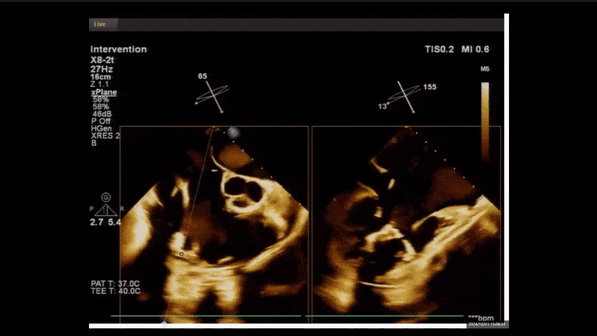

術前TEE評估

1、3D TEE顯示雙房及右室擴大,右室中段直徑40mm,右室FCA 52%。三尖瓣環TAPSE 22mm,三尖瓣環左右徑49mm,三尖瓣隔葉長度16mm,前葉長度21mm,后葉長度34mm,三尖瓣前隔gap 11mm,后隔gap 5.6mm,AP gap 12mm,診斷極重度功能性三尖瓣返流(Type I型三尖瓣:Torrential FTR 5+)。

2、彩色多普勒顯示:收縮期三尖瓣口返流束起源于后隔交界、前后葉之間及前隔交界,返流束縮流頸最大寬度27mm,三尖瓣返流口EOA=2.02cm2,返流容積124ml,收縮期三尖瓣返流峰值速度2.64m/s,返流峰值壓差28mmHg,PAPs 43mmHg,舒張期三尖瓣口平均跨瓣壓差1mmHg,肝左靜脈可見明顯逆向血流波。

術中經食道超聲輔助下可見LuX-Valve Plus夾持件抓捕瓣葉狀態良好,夾持件在位,室間隔錨定位置良好,假體瓣膜整體錨定狀態穩固。